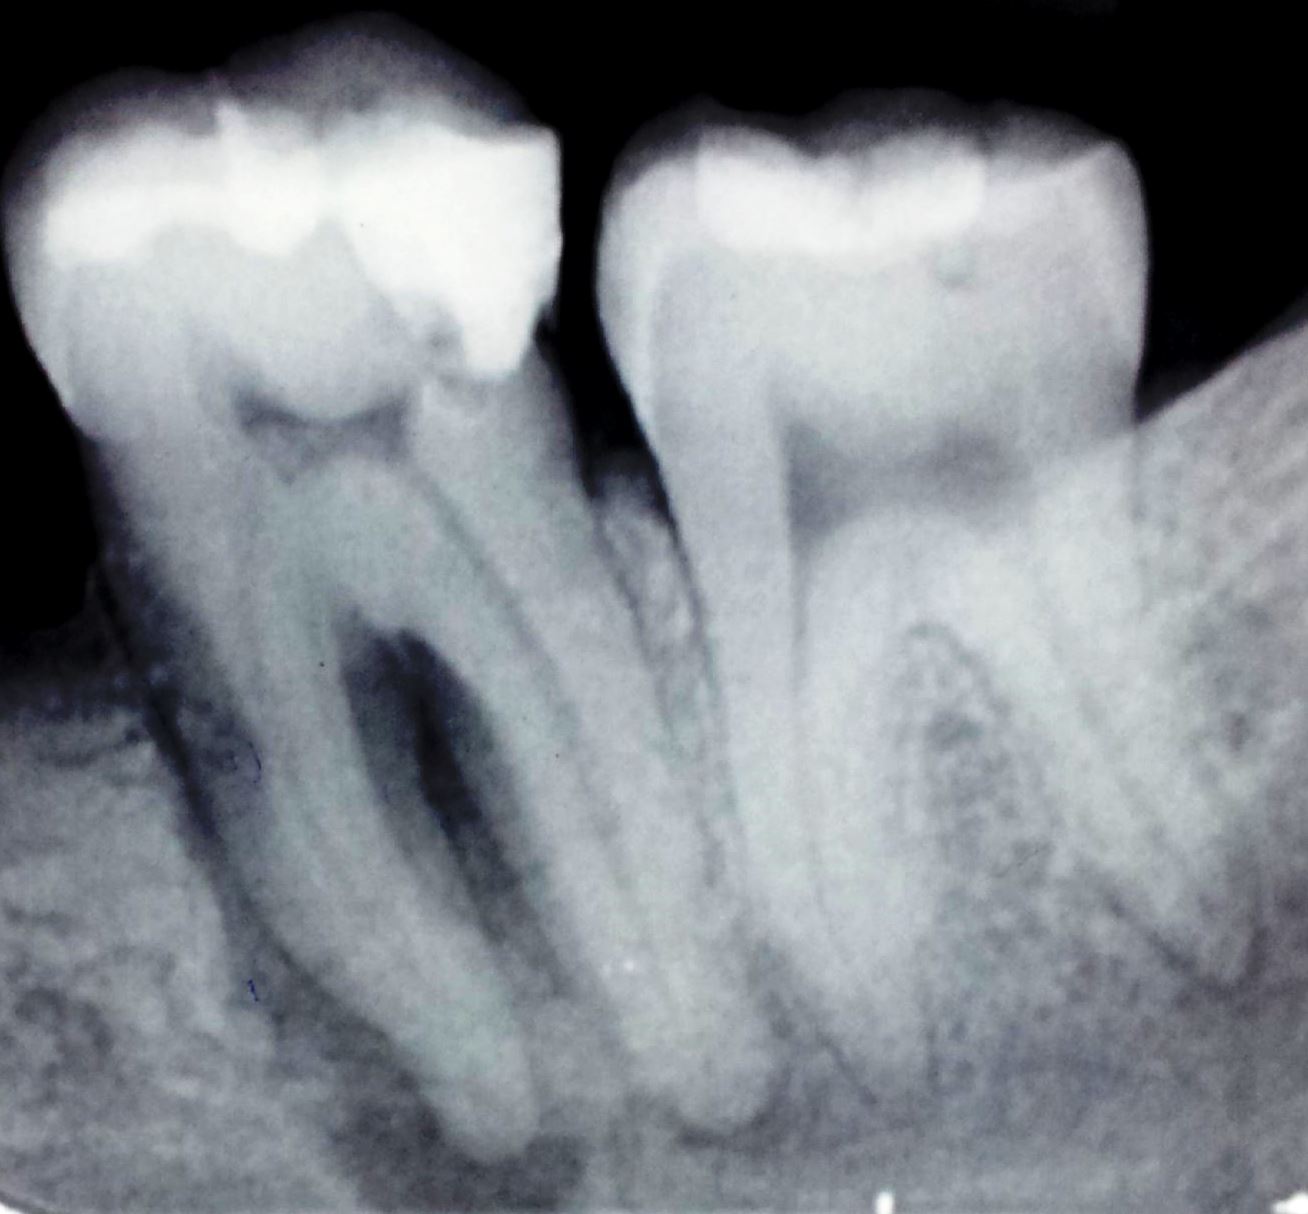

Endo Perio Lesion X Ray . This article will appraise the interrelationship between endodontic and periodontal diseases and provide biological and clinical evidence of. Dentists are likely to encounter lesions that have both periodontal and endodontic aetiological components; Classification of a disease (as presented by its clinical profile) is fundamental; The identification of its causes allows appropriate treatment.

The radiographs below show examples of grade 3 endoperio lesions Endo Perio Lesion X Ray The identification of its causes allows appropriate treatment. Classification of a disease (as presented by its clinical profile) is fundamental; This article will appraise the interrelationship between endodontic and periodontal diseases and provide biological and clinical evidence of. Dentists are likely to encounter lesions that have both periodontal and endodontic aetiological components; Endo Perio Lesion X Ray.